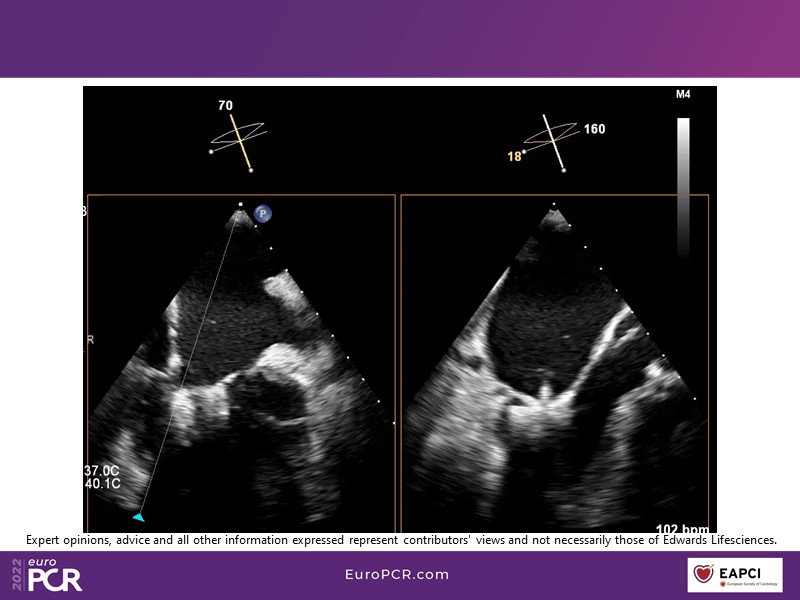

With study outcomes and clinical cases, this EuroPCR 2022 session will enable you to discuss the anatomical considerations that define suitable candidates for treatment of mitral regurgitation with the PASCAL platform and highlight key differentiators and tips and tricks for its use.

- To discuss which anatomical considerations define suitable candidates for the treatment of mitral regurgitation with the PASCAL platform

- To attend case-based discussions that will highlight key differentiators and tips and tricks when using the PASCAL platform to treat mitral regurgitation